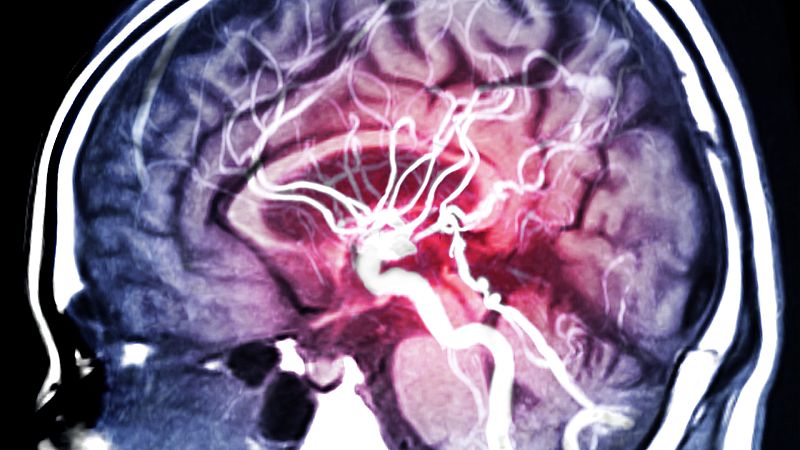

El sistema inmune participa en las alteraciones cerebrales que provoca la adicción al alcohol según han descubierto investigadores del Instituto de Neurociencias de Alicante. El estudio evidencia que el alcohol facilita la adicción cambiando la geometría de la sustancia gris del cerebro.